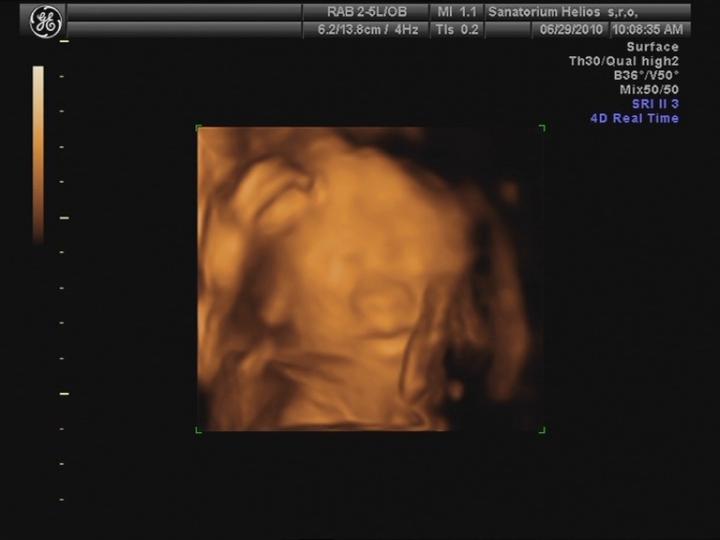

25.5. jsme vstoupili do 5. měsíce .... nečekaně se to pohlo 🙂